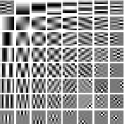

IV-A Transform Learning

To better understand the potential of the MRST model, we vary the number of layers and pre-learn transforms for ST, MRST2, MRST3, MRST5, and MRST7, which possess , , , , and layers, respectively. We used 7 slices of the Mayo Clinic data to train the models. For each model, we run 1000 to 2000 iterations of the learning algorithm to ensure convergence. Fig. 1 shows some of the learned transforms, with each transform matrix row displayed as a square patch for simplicity. The single layer transform displays edge-like and directional structures that sparsify the image. However, with more layers, finer level features are learned to sparsify transform domain residuals in deeper layers. Nonetheless, transforms in deep layers could be more easily contaminated with noise in the training data, since the main image features are successively filtered out over layers.